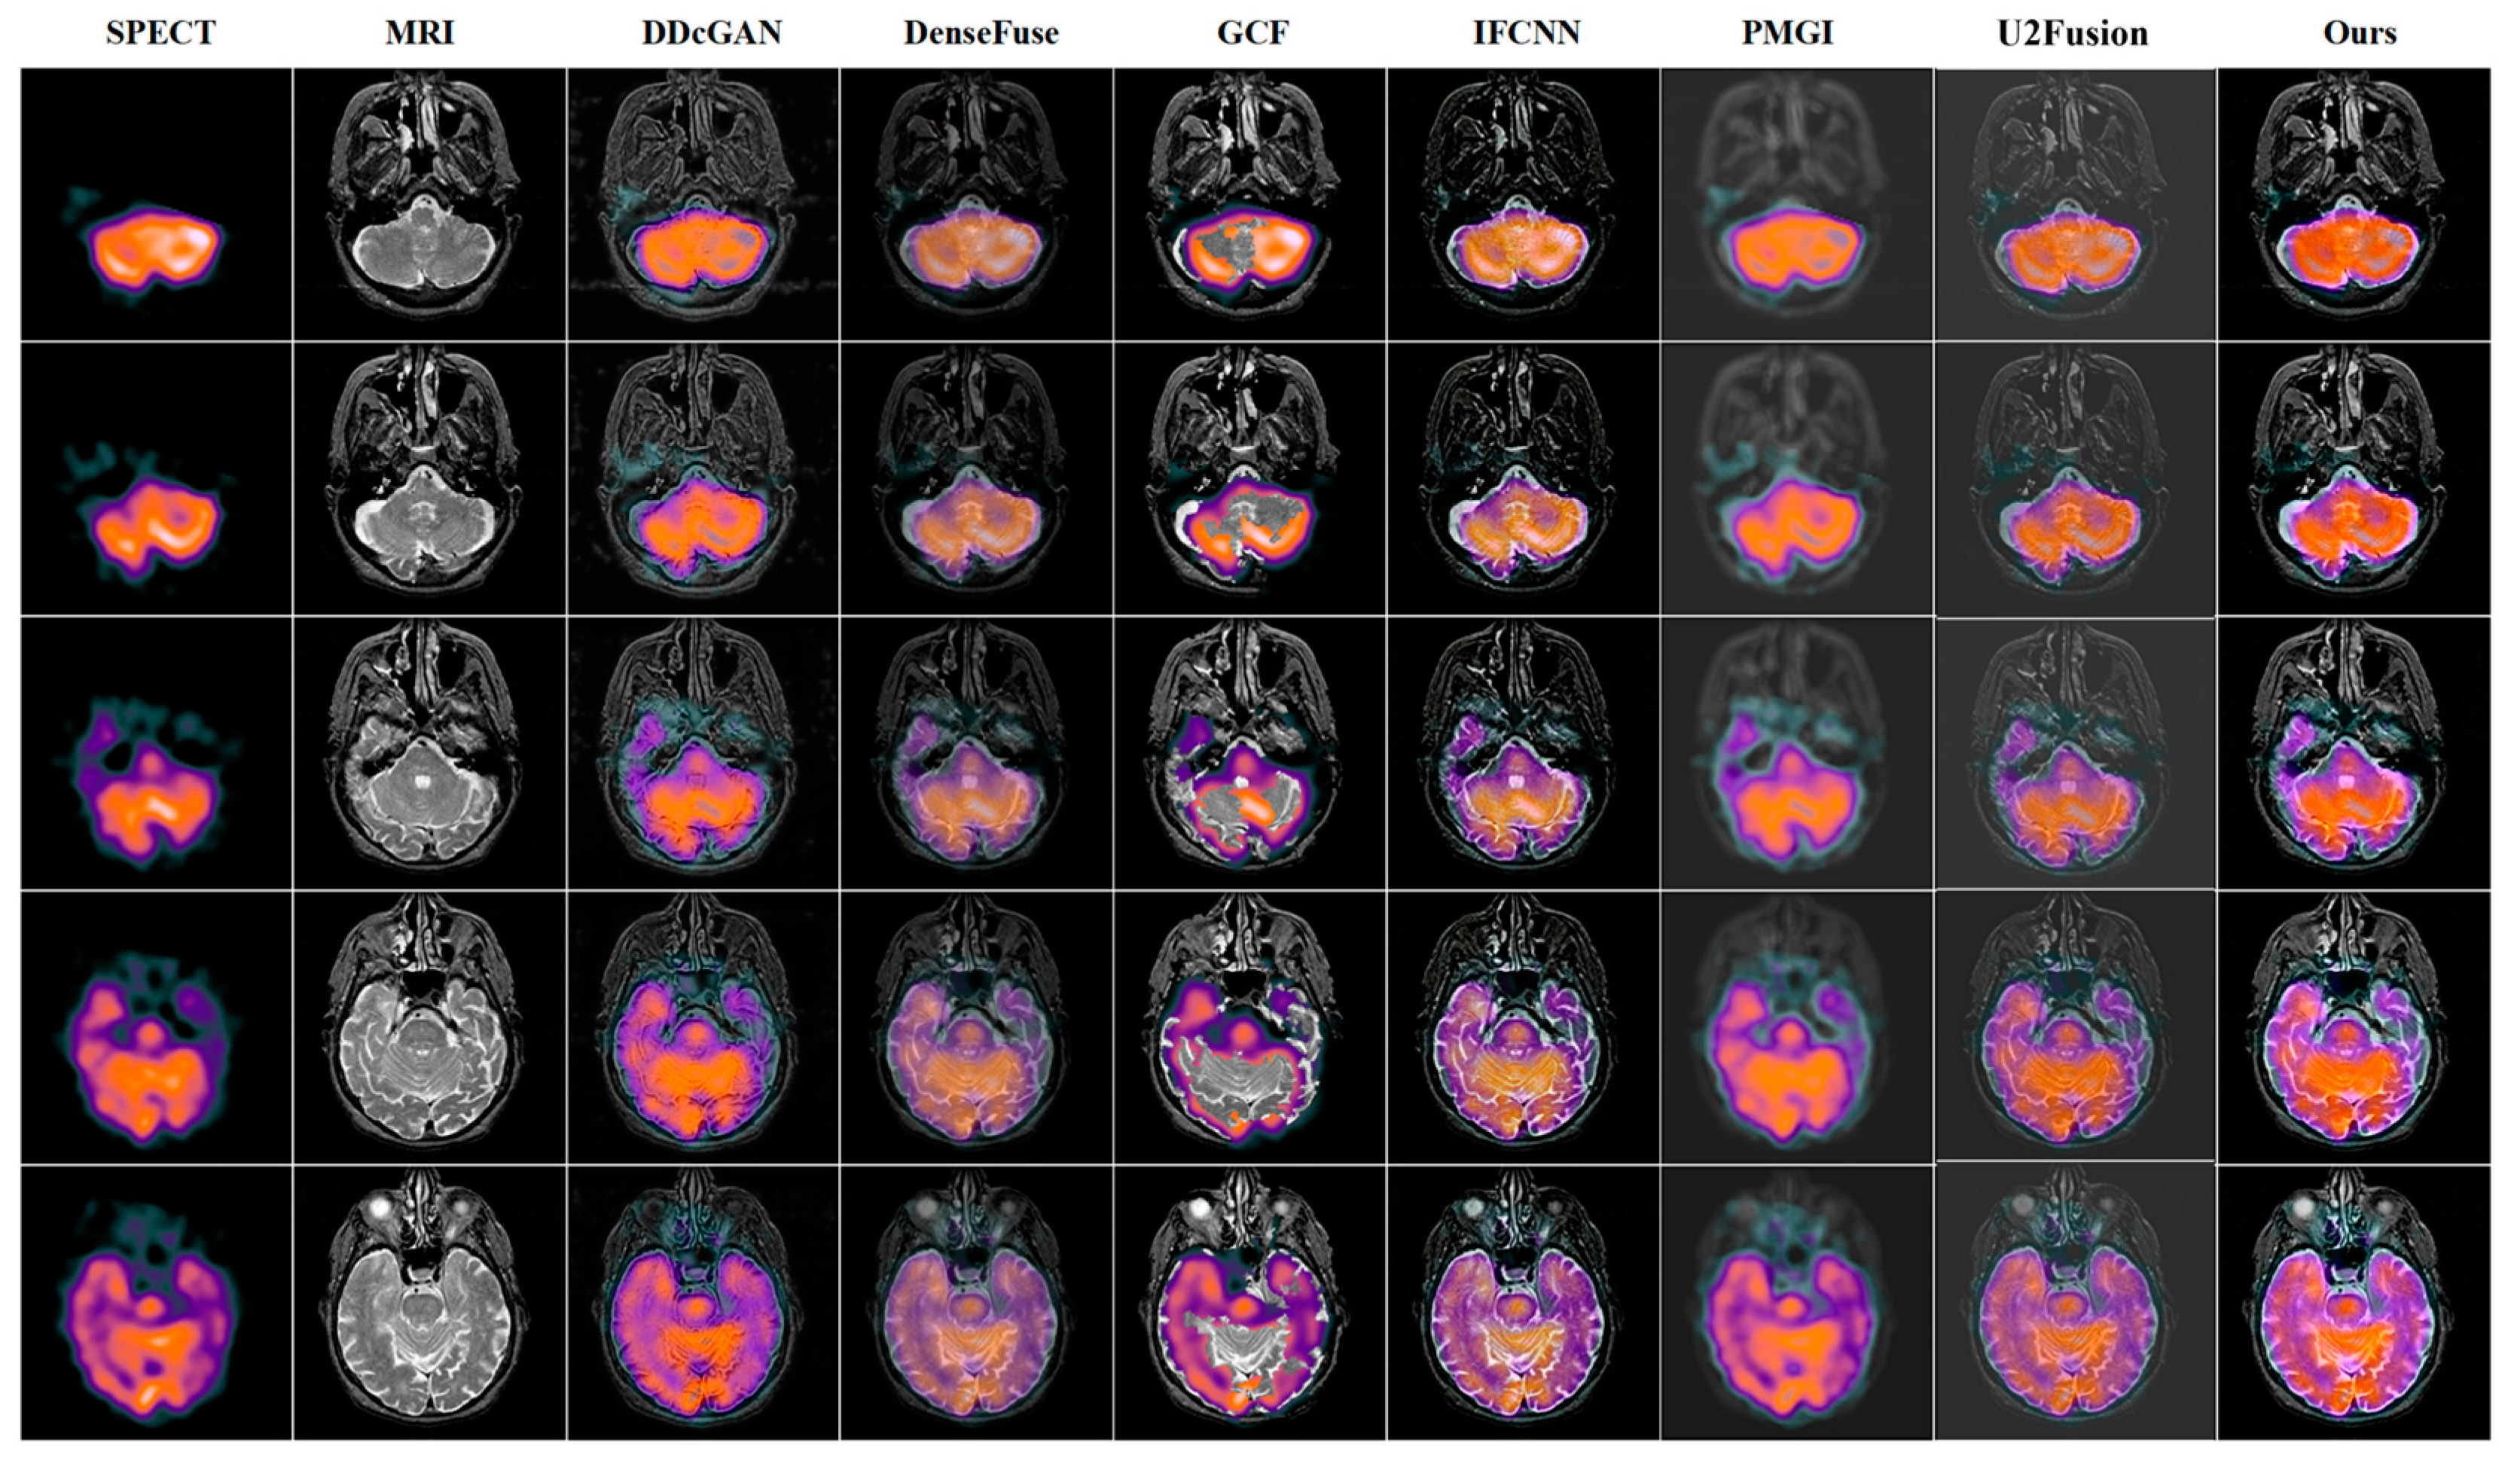

4.3. Quantitative and Qualitative Comparison Results

SPECT-MRI | DDcGAN | DenseFuse | GCF | IFCNN | PMGI | U2Fusion | Ours |

---|---|---|---|---|---|---|---|

AG↑ | 4.7542 | 3.4322 | 5.9096 | 6.1458 | 1.9178 | 3.8571 | 6.1660 |

EI↑ | 50.1068 | 36.6158 | 62.9763 | 64.8819 | 20.7479 | 39.1411 | 65.3377 |

Qabf↑ | 0.2334 | 0.1444 | 0.3896 | 0.4065 | 0.0798 | 0.2113 | 0.4353 |

Qcv↓ | 844.875 | 560.090 | 317.356 | 1009.200 | 2473.292 | 886.6785 | 178.168 |